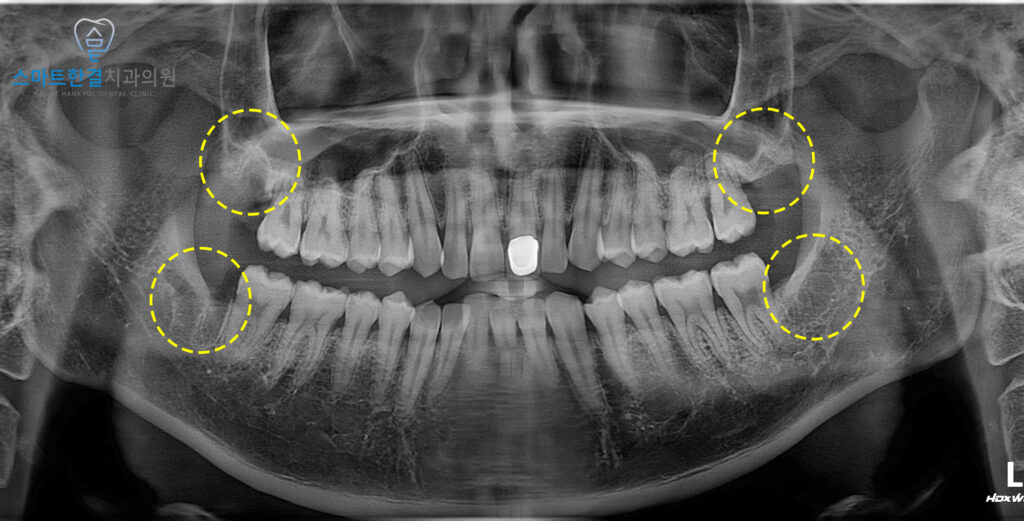

이후 잇몸이 어느 정도 아물고 난 뒤

오른쪽까지 발치를 하였습니다^^

위쪽 사랑니는 상악동과 가까웠으며,

아래쪽은 신경관과 가까워

상악동 개통 또는 신경관 손상의

우려가 있었으나 화서동치과에서는

치료 전 3D CT를 촬영해 거리와 위치를

확인 후 진행하여 보다 안정적으로

발치를 할 수 있었어요.